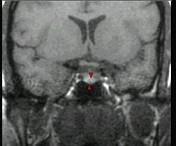

女,38岁,头痛、闭经,MRI检查如图,选择最可能的诊断()A.垂体囊肿B.垂体梗死C.转移瘤D.垂体微腺瘤E.垂体脓肿

问题 女,38岁,头痛、闭经,MRI检查如图,选择最可能的诊断()

选项 A.垂体囊肿 B.垂体梗死 C.转移瘤 D.垂体微腺瘤 E.垂体脓肿

答案 D